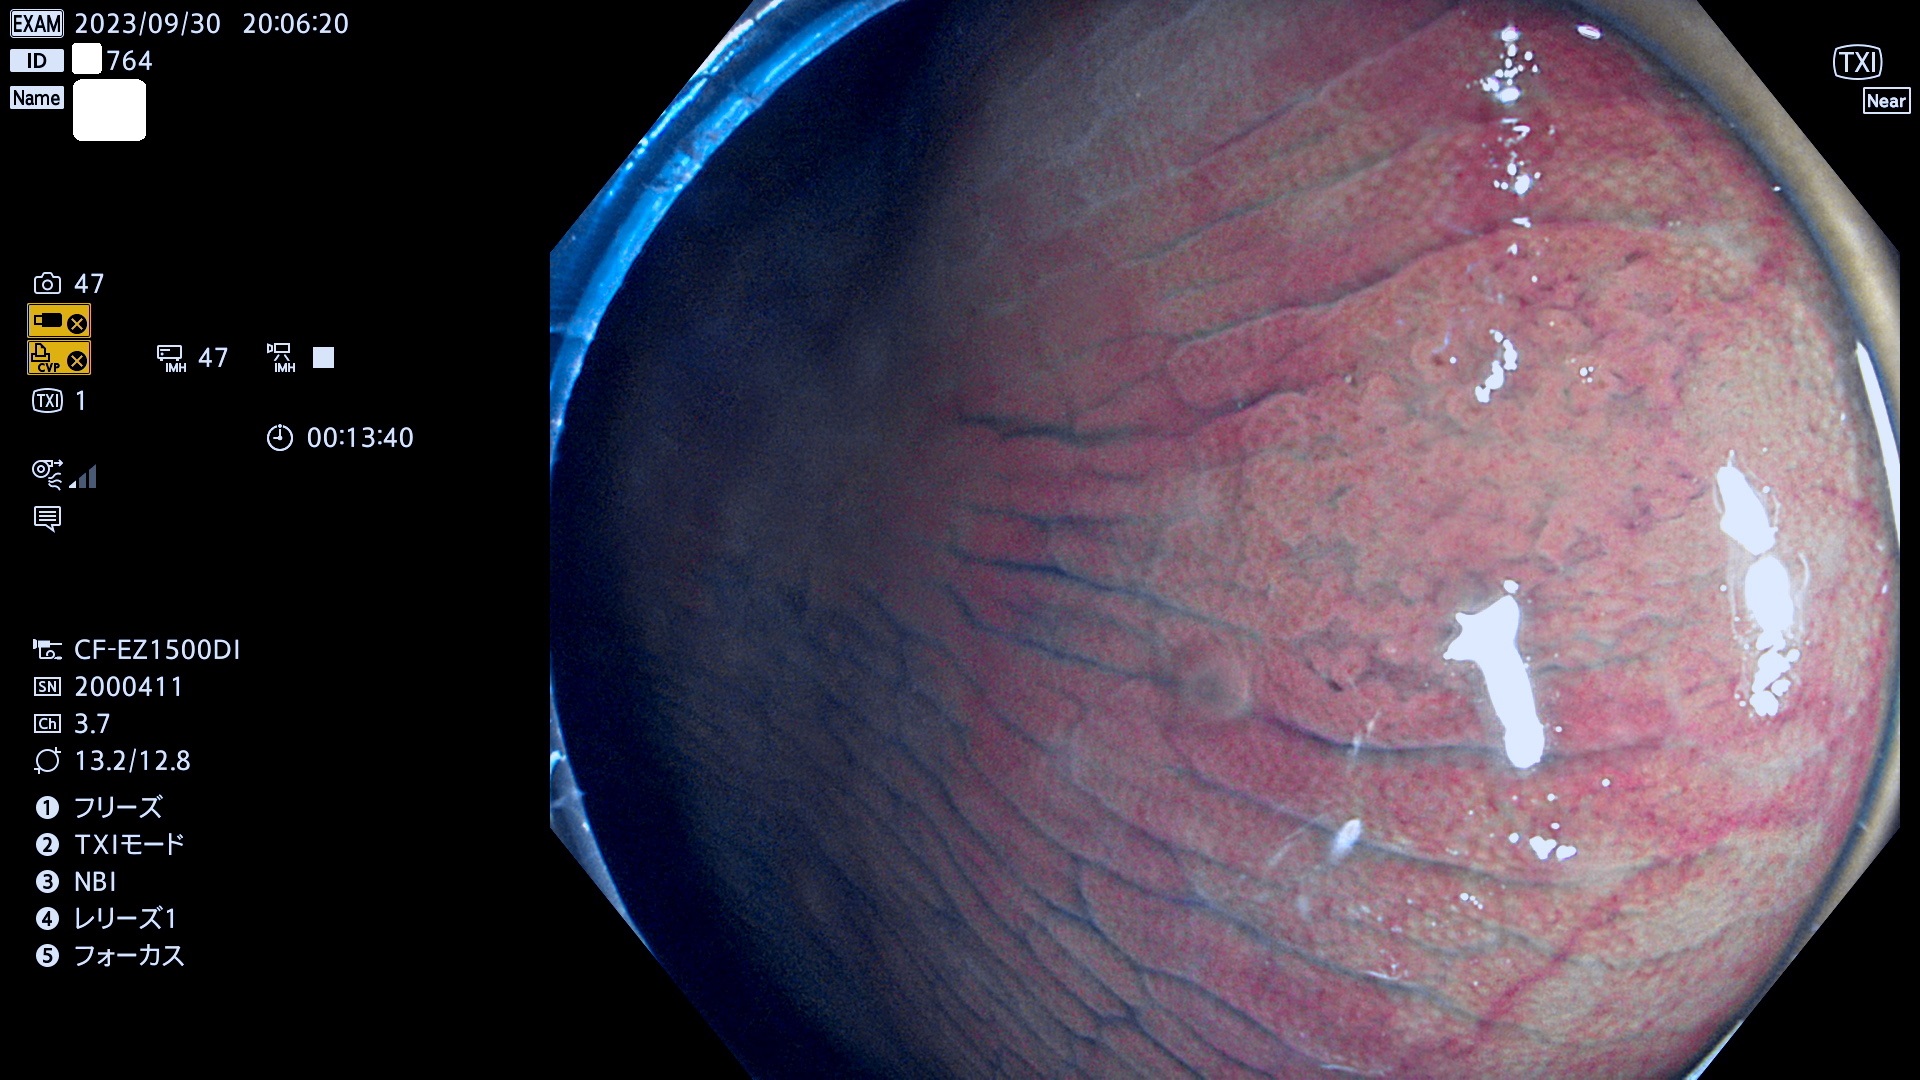

表面型腺腫(Flat Adenoma)の中で、完全に平坦な物をUb、陥凹している物をUcと呼びます。平坦隆起型(Ua)よりも、発見が難しく危険な病変です。このタイプは「内視鏡後・大腸癌の重要犯人」であり、この発見率は「腺腫発見率」よりも、重要な意味があります。

毎週の検査(木・金・土・日)に発見されたUb、Uc型・腺腫を、その週の日曜の夜にUPし1週間、提示します。

抽出の対象期間 2023年9月28日(木)〜10月1(日)の4日間(48件の検査)8件